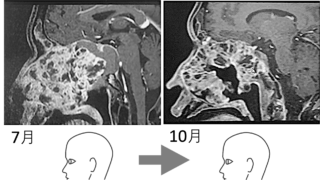

肺ガンの患者さんである。

56歳。自営でデザイナー。できる女性である。

病院に通院はしているが、積極的な治療を断っている。千葉からここ奈良まではるばる当院に来院、1〜2日で2〜3回の短期集中の治療をしつつ経過をみる。

重症ではあるが、よい経過をたどりつつある…と見ていた。

だが、だんだん声がかすれ、咳こむ。感染症かとも思われたが、そうではなかった。

気道が狭まるような呼吸をし出したのである。ガンが気管を塞ぎ始めたのだ。

8月22日。わずか2周間後だった。

初診はわずか3ヶ月前。8回奈良に来て、19回の治療のご縁があった。